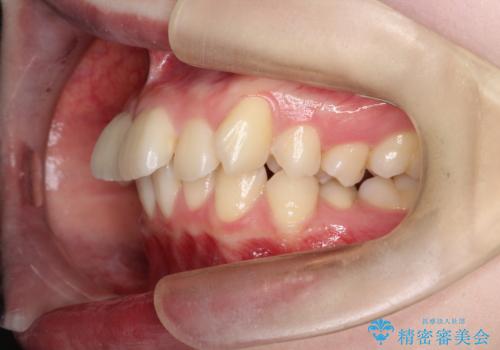

- 前歯が突き出ていることによる口元の突出感と、下顎が右側にズレていること(右方偏位)を主訴にご来院されました。

精密検査の結果、歯を並べるスペースの不足に加え、上下の歯列の正中(中心)が大きくズレていることが確認されました。突出した口元を下げ、顎の左右バランスを整えるためのスペースを確保するため、右上・左上・左下の4番目(第一小臼歯)を計3本抜歯する計画を立案。装置は、治療中の見た目にも配慮し、目立ちにくい審美ワイヤーを選択しました。

治療は、抜歯によって得られたスペースを活用し、前歯を後方へ移動させながら上下の中心を一致させる緻密な調整を行いました。

特に下顎の右方偏位に対しては、ワイヤーによる繊細なコントロールを行い、左右の咬合バランスを整えることに重点を置きました。2年半の治療期間を経て、突出していた前歯は理想的な位置に収まり、顎のズレも大幅に改善されました。